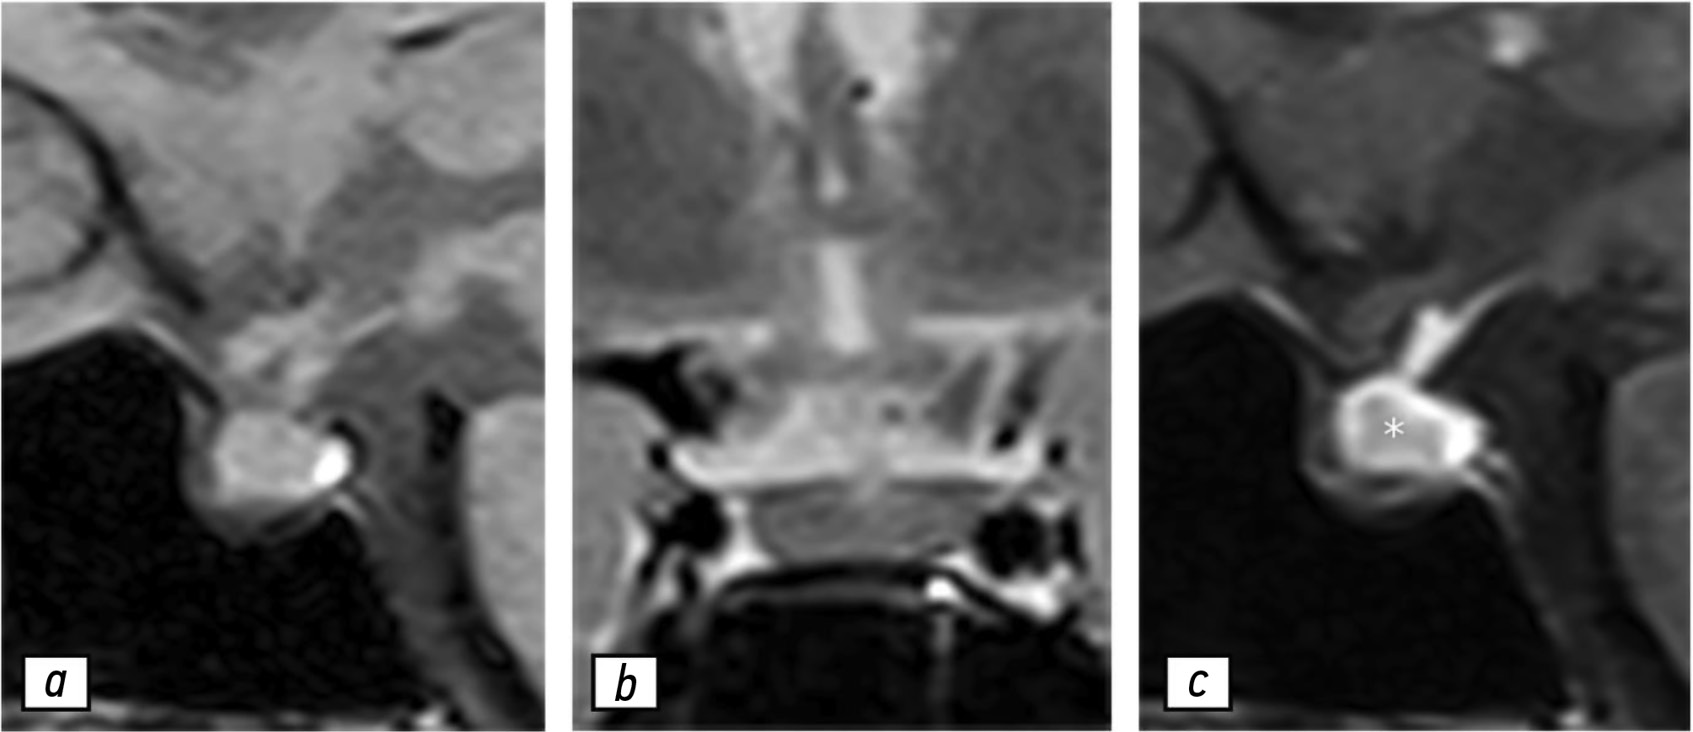

家庭性转铁蛋白淀粉样变性与高脂蛋白(a)血症合并症: 脊柱管狭窄患者的临床病例

遗传性转铁蛋白淀粉样变性是一种罕见的系统性进展性常染色体显性遗传疾病,与不可溶性的淀粉样纤维在外周神经系统、心脏及其他器官的细胞外沉积有关。该病的特征性症状或“红旗”包括症状性脊柱管狭窄。脂蛋白(a)被归类为动脉硬化性脂蛋白,因此其在血浆中的浓度升高被认为是心血管疾病和脑血管疾病的显著危险因素。目前关于转铁蛋白淀粉样变性与脂蛋白(a)浓度之间关系的信息仍较为匮乏。

本文描述了一例患者的临床病例,该患者长期患有高血压,血压升高至150/90 mm Hg,持续5年。在2021年6月2日至25日期间感染新冠病毒后,患者出现血压升高至290/150 mm Hg,并伴有左胸部刺痛,持续20-30分钟,无与体力活动相关,服药后缓解,同时伴有颈椎和胸椎区域的疼痛。在降压治疗的背景下,血压稳定至110/70 mm Hg。在进一步检查中发现患者存在血脂异常,低密度脂蛋白胆固醇浓度升高至4.53 mmol/L,脂蛋白(a)浓度升高至1.46 g/L。通过超声多普勒检查发现患者有颈动脉粗大干的动脉粥样硬化,且右侧内颈动脉起始部狭窄至20%。心脏超声检查显示左心室壁、房间隔和二尖瓣叶增厚,但射血分数正常。通过脊柱磁共振成像发现患者有颈椎脊柱管狭窄(СV–VI)。基因检测揭示患者及其直系亲属和家族成员具有转铁蛋白基因的核苷酸序列变异(Chr18: 29171879 G>A, p.Arg5His),且该变异处于杂合子状态。文章讨论了使用Tafamidis进行特异性抗淀粉样变性治疗,并为患者开具了降脂药物治疗。

对于患有症状性脊柱管狭窄并且左心室壁增厚的患者,即便存在高血压,也应进行综合检查,以便及时诊断和合理治疗淀粉样心肌病。因此,我们首次描述了家庭性转铁蛋白淀粉样变性与高脂蛋白(a)血症的临床病例。